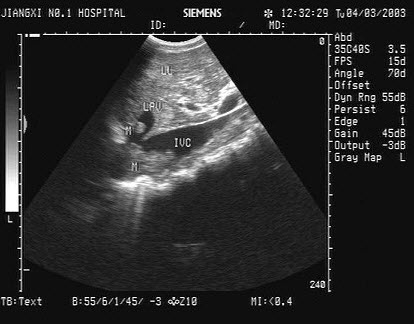

13、单项选择题

女,25岁,因急性胰腺炎禁食5天。声像图如图所示。结合超声声像图,诊断为()